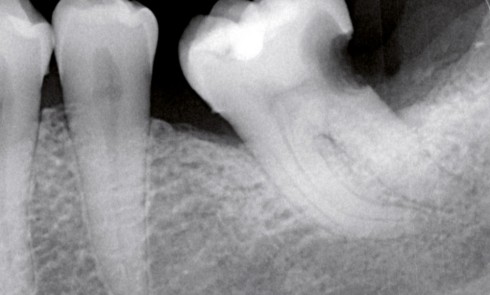

Article réservé à nos abonnés La cavité d’accès a minima

La perte de substance tissulaire de l’organe dentaire, qu’elle soit d’origine carieuse, traumatique ou consécutive à une thérapeutique de préparation...